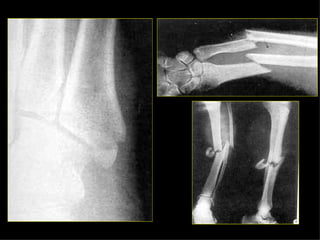

CADERA FEMUR RODILLAPIERNA TOBILLO PIE Eversión Inversión

CADERA FEMUR RODILLA PIERNA TOBILLO PIE Eversión Inversión